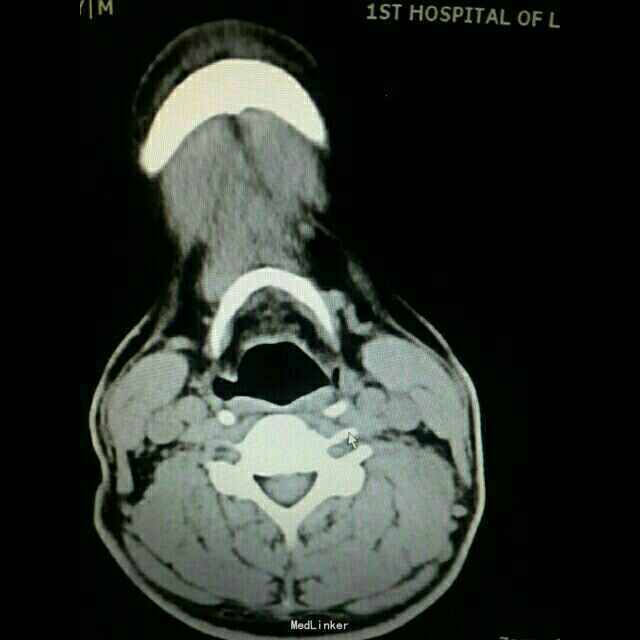

专科检查:颈部左侧胸锁乳突肌后缘中点可触及一大小约1.5×2.0cm肿物,类梭型,界清,质硬,无疼痛,活动度良好。 颈部CT及核磁检查

诊断:颈部左侧纤维瘤病。全麻下行:颈部左侧肿物切除术+神经移植术(备)。术中探查肿物与臂从神经界限清,排出神经纤维瘤可能,考虑肌肉来源肿瘤。